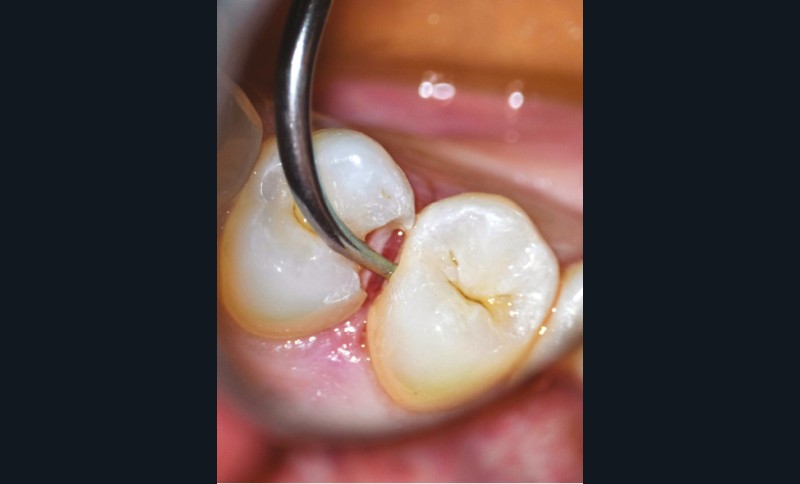

- soit de façon invasive a minima. Cette économie tissulaire peut se faire notamment avec l’utilisation de fraises adaptées et minimalement invasives (fig. 4).

• Traitement invasif a minima : il concerne les lésions carieuses cavitaires ou non avec atteinte dentinaire (à partir du 1/3 moyen dentinaire), soit ICDAS 3 à 6. Dans ce cas, la priorité est de préserver la dent d’une effraction pulpaire éventuelle (recommandations de l’ESE) [4]. C’est pourquoi, lors du traitement de lésions carieuses profondes (ICDAS 4 à 6), il faut dans tous les cas réaliser une éviction sélective, réaliser une préparation a minima (favoriser les préparations de type fente (« slot ») ou tunnel lorsque l’indication se pose) et utiliser un matériau de restauration de choix, soit composite, soit un ciment verre ionomère (CVI), soit des matériaux à base de silicate de calcium ou encore les nouveaux composites enrichis en minéraux (fig. 7 à 9). Ces préparations a minima peuvent être réalisées avec des fraises de petits diamètres (fig. 10 et 11).